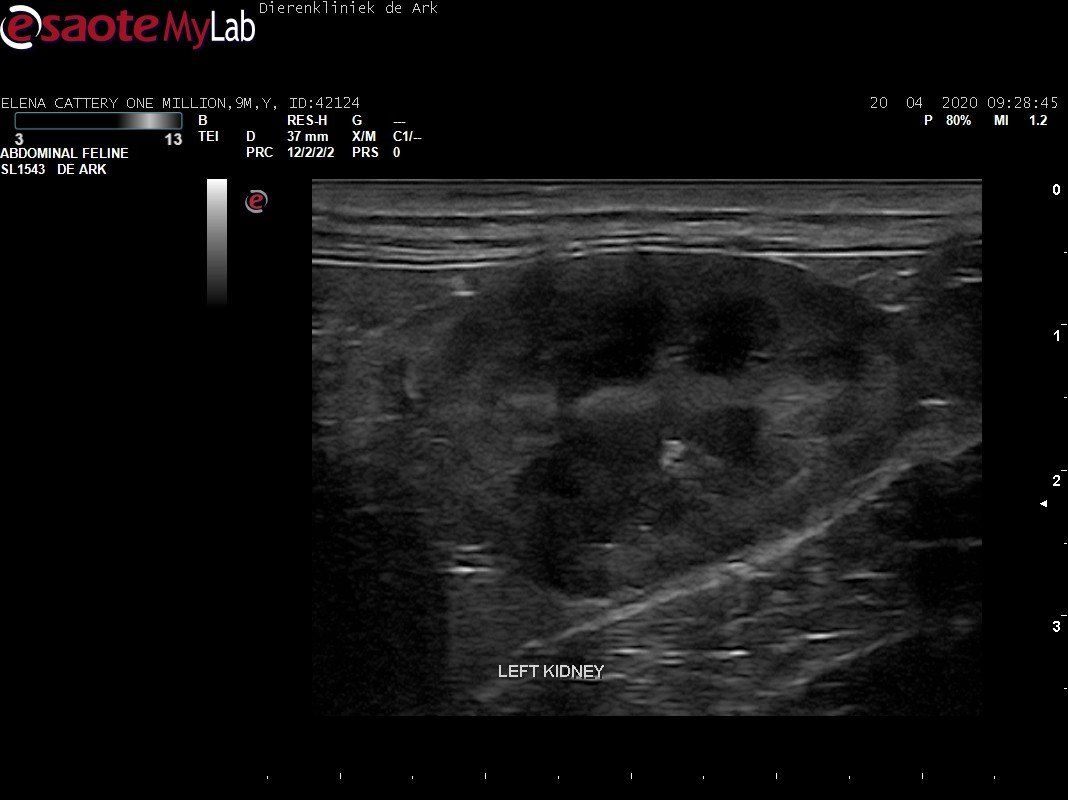

3,200 kg , echo en nieuw bloedonderzoek gedaan wat perfect ging door middel van gapabetine

Voor de garanties en om recht te hebben op medicatie bij herval eist Mutian diverse onderzoeken en controle momenten. Dit zijn bloedonderzoeken maar ook zoals hieronder te zien is echo's. Elana is volledig gecontroleerd op afwijkingen, gelukkig waren de echo's goed.

Ook de bloeduitslagen waren in orde, we kregen groen licht om te stoppen met behandelen en de wachtperiode in te gaan.